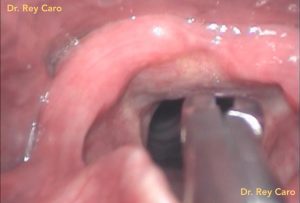

Caso 1: Pólipo de cuerda vocal izquierda.

Caso 2. Pólipo de cuerda vocal derecha

Caso 2. Mucocele (quiste) de ventrículo laríngeo derecho